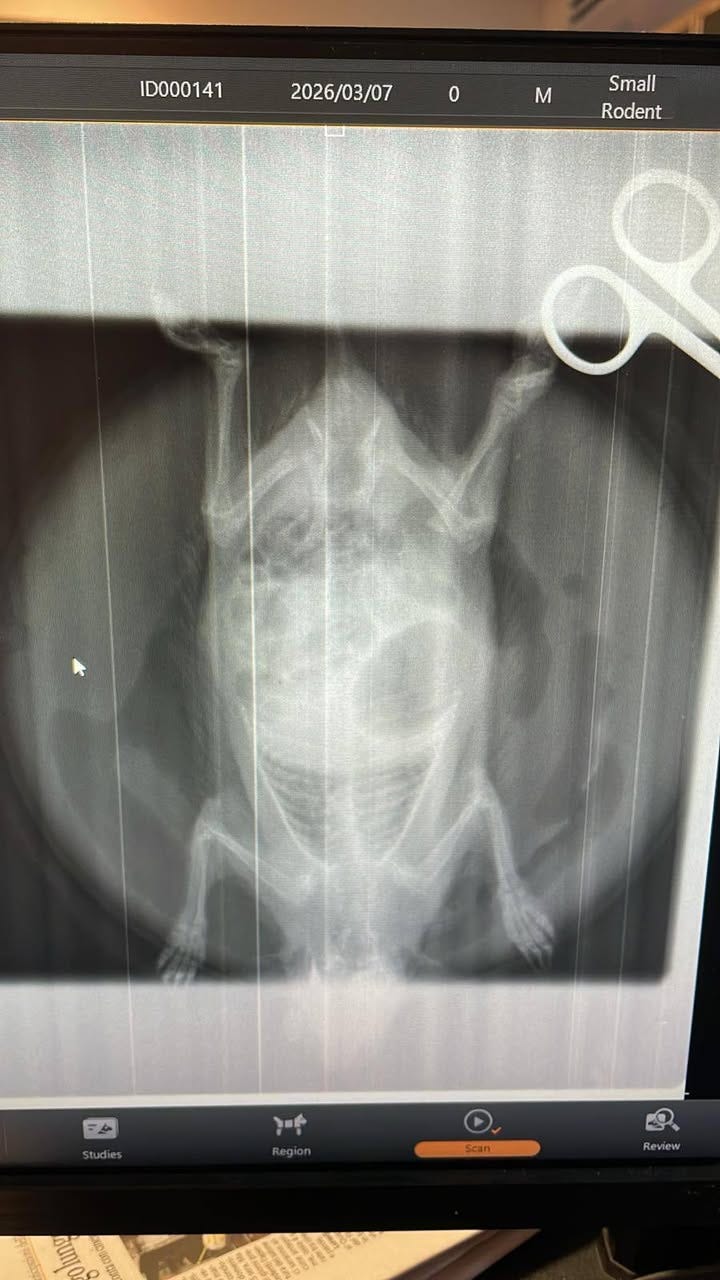

Controlli veterinari:

Una lastra di controllo ha confermato la frattura dell’arto posteriore e la lussazione dell’anca.Come sta ora: